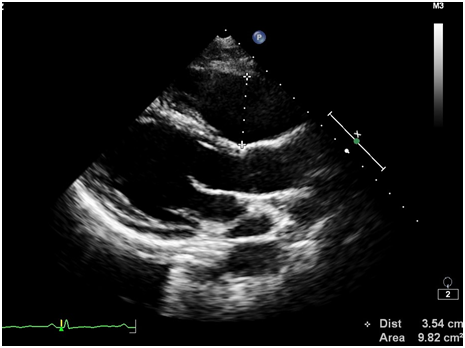

Ürəkdə hər hansı struktur dəyişlikliyin olub olmadığını bilmək üçün 2D, M, TDI-PW rejimlərindən istifadə etməklə exokardioqrafik müayinə aparıldı. Müayinə zamanı sağ mədəciyin (RV) sərbəst divarında çapıq toxumasına bənzər hiperexogen sahə, sağ mədəciyin genəlməsi və sistolik funksiyasının zəifləməsi (FAC – 30.5%, N > 35%) aşkarlandı (şəkillər 2-8). Bunun ardınca təyin olunan EKQ-nin 24 saatlıq Holter monitorlamasında çoxlu miqdarda (politop, qrupşəkilli, triplet) mədəcik ektopiyası qeydə alındı (şəkil 9). Bu nəticələrə asasən xəstədə aritmogen sağ mədəcik displaziyasına (ARVD, ARVC) şübhə yarandı və ürəyin MRT olunmasına qərar verildi. Ürəyin MRT müayinəsində aritmogen displaziyaya uyğun görüntülər qeydə alındı.